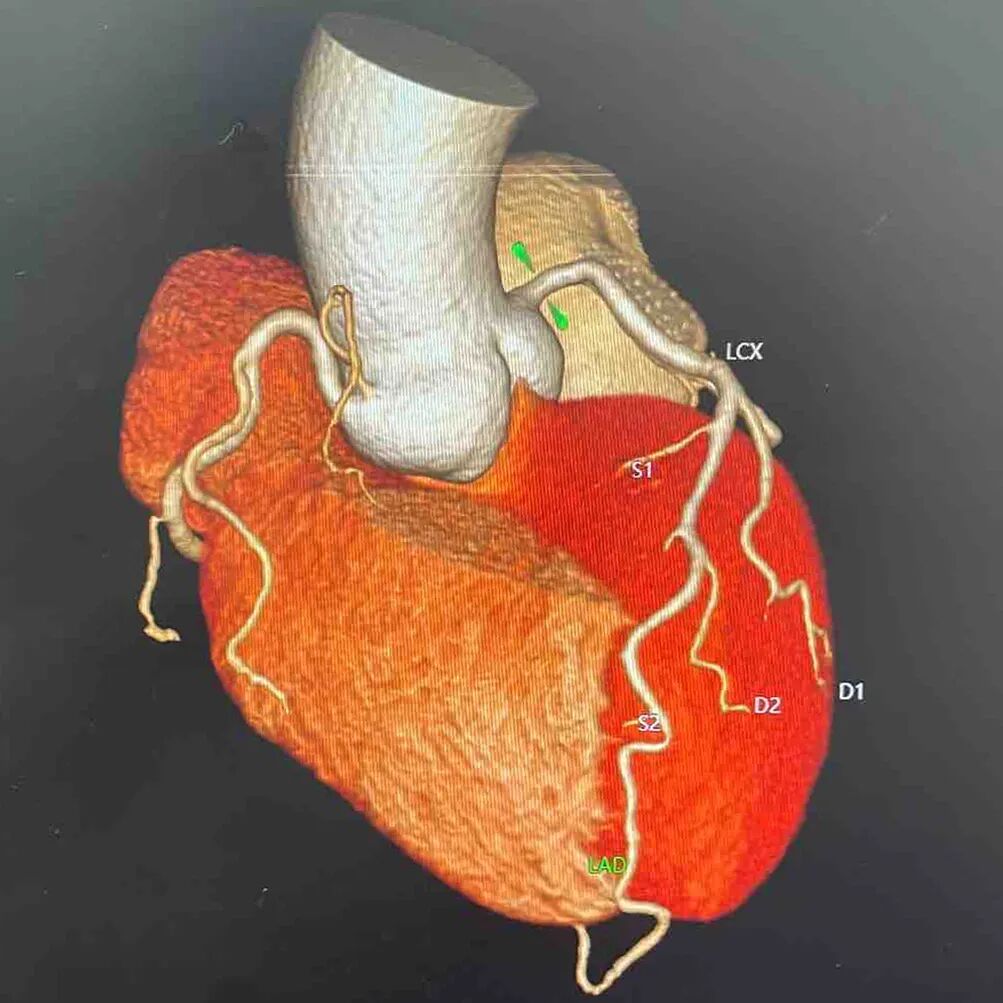

CT相当于“立体X光”,是通过X射线环绕扫描,一层一层获取人体的断面图像,再重组成三维图像。

这项检查能清晰显示全身各器官的细微病变,如早期肺癌、脑出血等,是发现早期肿瘤、评估复杂伤情的重要工具。

320排CT(上图)

冠脉CTA重建的3D影像(右图)

虽然拍单次CT比拍单次X片的辐射剂量高,有“做一次CT相当于拍几十到几百次X光”的说法,但做一次低剂量胸部CT的辐射量约1mSv,口腔CT这类局部检查辐射量更低。

我院的320排CT、口腔锥形束CT西门子数字化X线机都是超低剂量辐射,不管是拍CT、冠脉CTA还是牙片、X片等,辐射剂量都在标准范围内。